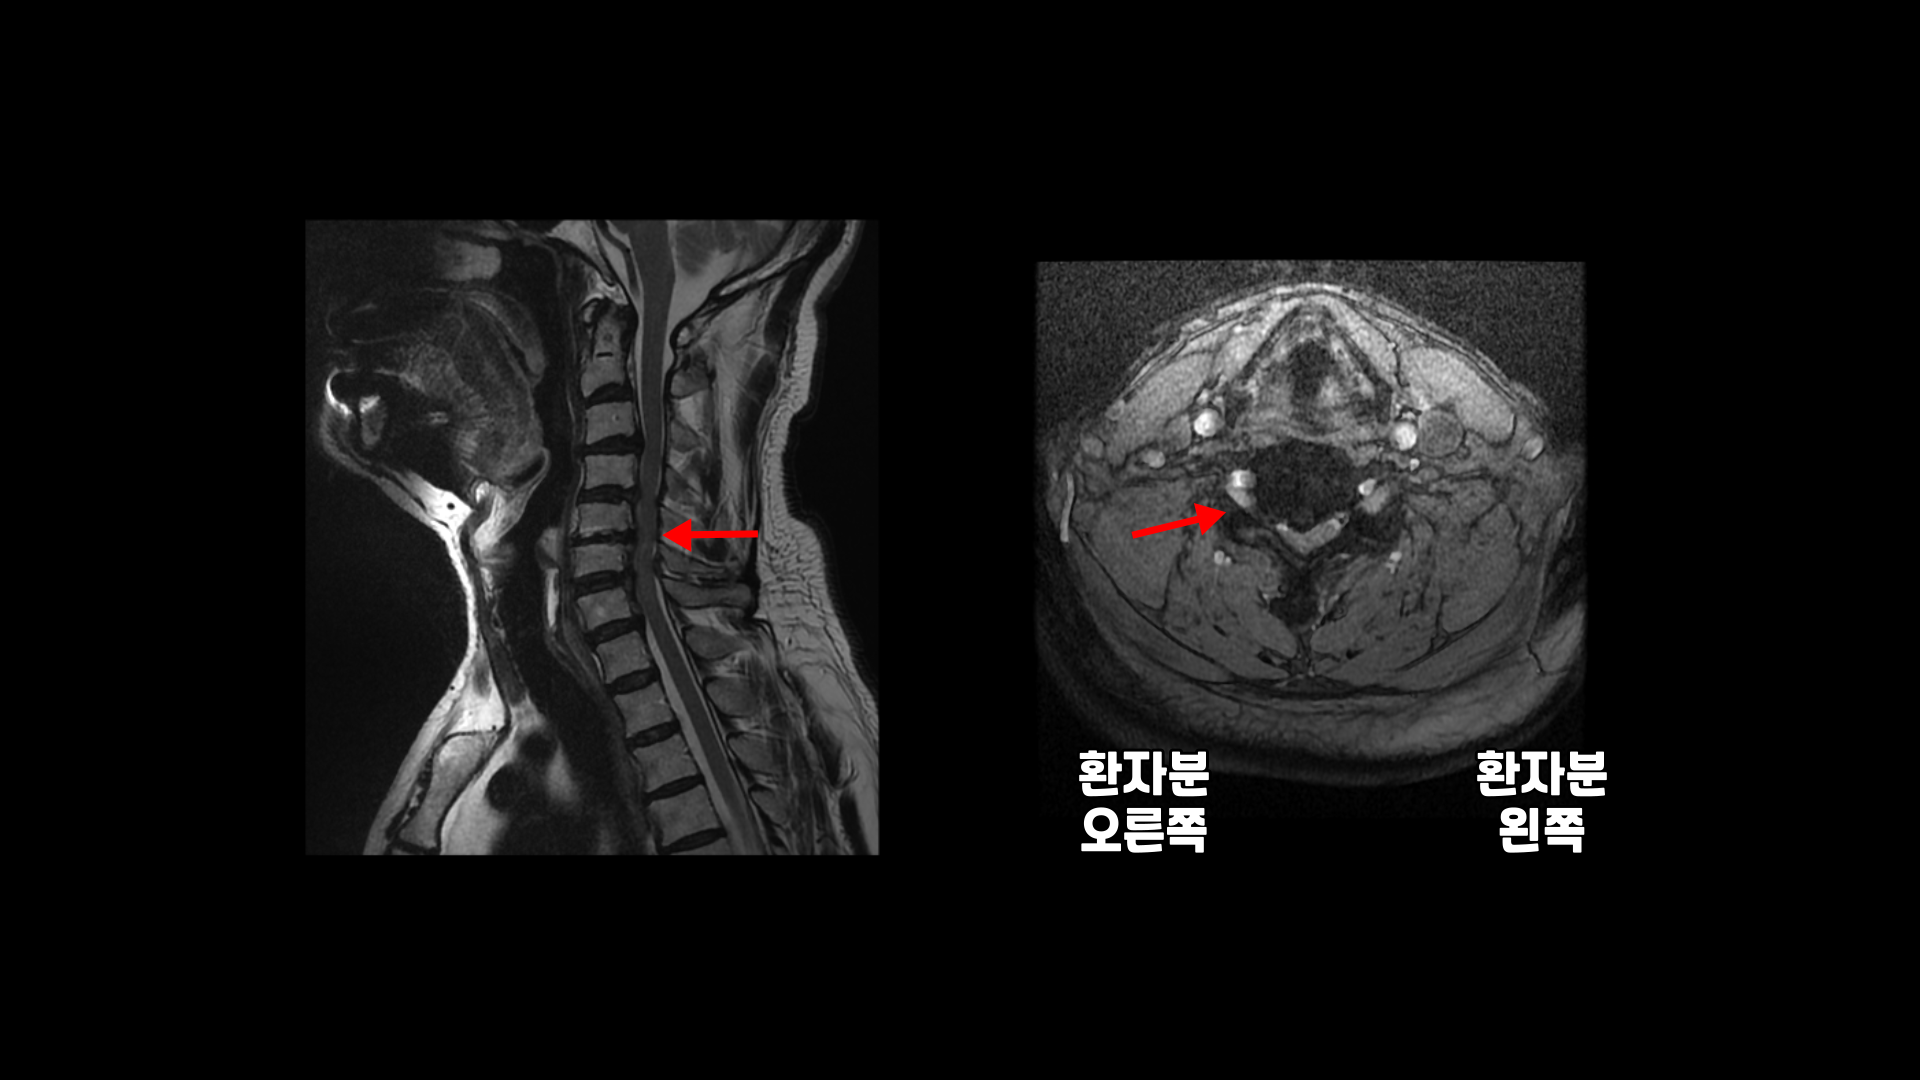

팔의 통증과 저림, 숟가락질과 젓가락질이 어려운 경추척수증 환자분의 MRI 상태 및 증상은?

목의 3번 4번과 4번 5번에는 가운데 쪽으로 디스크 돌출이 있고

5번 6번 문제가 제일 심각한데, 가운데 우측으로 목디스크 파열이 심하게 있습니다.

오른쪽으로 보시다시피 신경 나가는 길이 디스크와 협착으로 많이 막혀 있고 척수 신경에는 경추척수증, 즉 척수신경의 손상이 보입니다.

6번 7번과 7번 흉추 1번 디스크도 가운데로 밀려 나와있습니다.

이 환자분의 오른쪽 팔의 통증과 젓가락질이 안 되는 증상은 척수증보다는 목디스크 파열과 경추협착으로 인한 증상으로 보입니다. 즉 척수증은 있지만 척수증 관련된 증상은 없어 보입니다.

참고로 목디스크나 경추협착증, 척수증 등의 목 질환은 허리 질환과 달리 통원 치료가 가능한 경우가 매우 많습니다. 이 환자분도 통원 치료를 받으셨습니다. 또 목 질환에 대한 근육 재활치료의 장점은 치료가 허리보다 훨씬 더 빠르다는 겁니다. 이 환자분은 한쪽 다리에 오래된 저림 증상과 방사통이 있으셨습니다. 처음에 척수증 증상이 아닐까 해서 검사해봤는데 허리디스크 파열로 인한 다리 저림이었습니다. 목디스크를 치료하면서 동시에 허리도 치료해 드렸습니다. 이분의 목디스크와 협착의 치료 결과는 어떻게 되셨을까요? 환자분의 재활치료 결과가 궁금하시다면 아래 썸네일을 클릭해 모커리한방병원 홈페이지에 로그인하신 후 치료 후 결과 영상을 꼭 보시길 바랍니다.